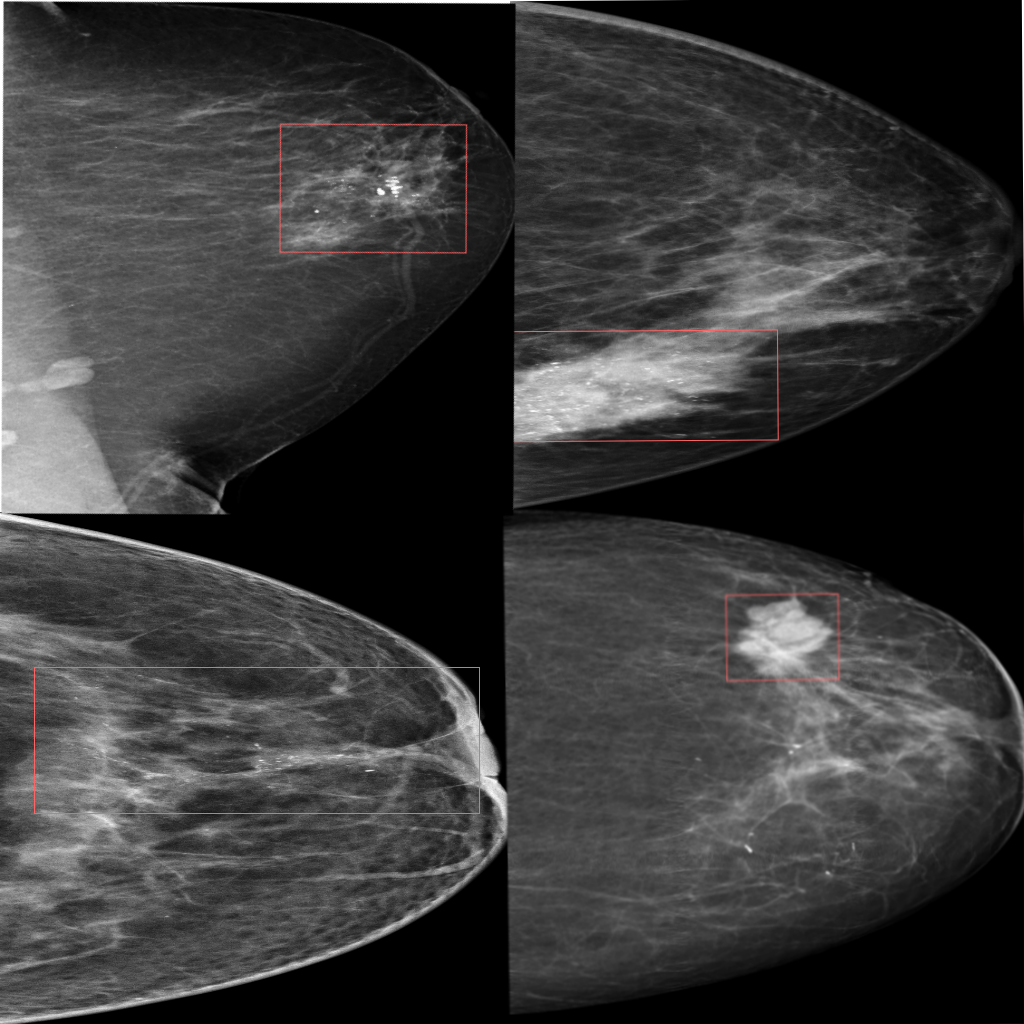

T.C. Sağlık Bakanlığı & TÜSEB destekli. Uzman radyolog etiketli ~1000 mamografide BIRADS sınıflandırma ile kitle & kalsifikasyon tespitinde %90+ başarı